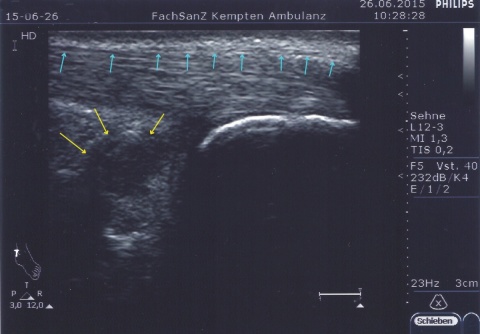

Ein einfacher Test zur Abgrenzung von einer Ruptur der Sehne mit Hämatom, Schwellung und eventuellem Tasten einer Delle ist nach wie vor der Simmonds-Thompson-Test (Plantarflexion des Fußes durch Kompression der Wadenmuskulatur bei intakter Achillessehne). Wie in der Kasuistik beschrieben, erfolgt die weitere Diagnostik mittels Sonographie der Ferse zur Darstellung einer Verdickung, Hypervaskularisation oder Zunahme von echoarmen Arealen. Zudem sollte eine Röntgenuntersuchung durchgeführt werden, um eine mögliche Haglund-Exostose zu detektieren. Eine Kernspintomographie der betroffenen Ferse eignet sich sehr gut zur Darstellung sowohl von strukturellen Veränderungen der Achillessehne, als auch begleitender Entzündungszeichen (siehe Abbildung 3).

Im Rahmen der Diagnostik in der truppenärztlichen Sprechstunde kann neben der obligaten klinischen Untersuchung eine sonographische Darstellung beider Achillessehnen im Seitenvergleich erste Anhalte für die Ursache der Beschwerdesymptomatik liefern.

Bildquellen: Abbildungen 1 und 2: P. Hoth, Kaufbeuren